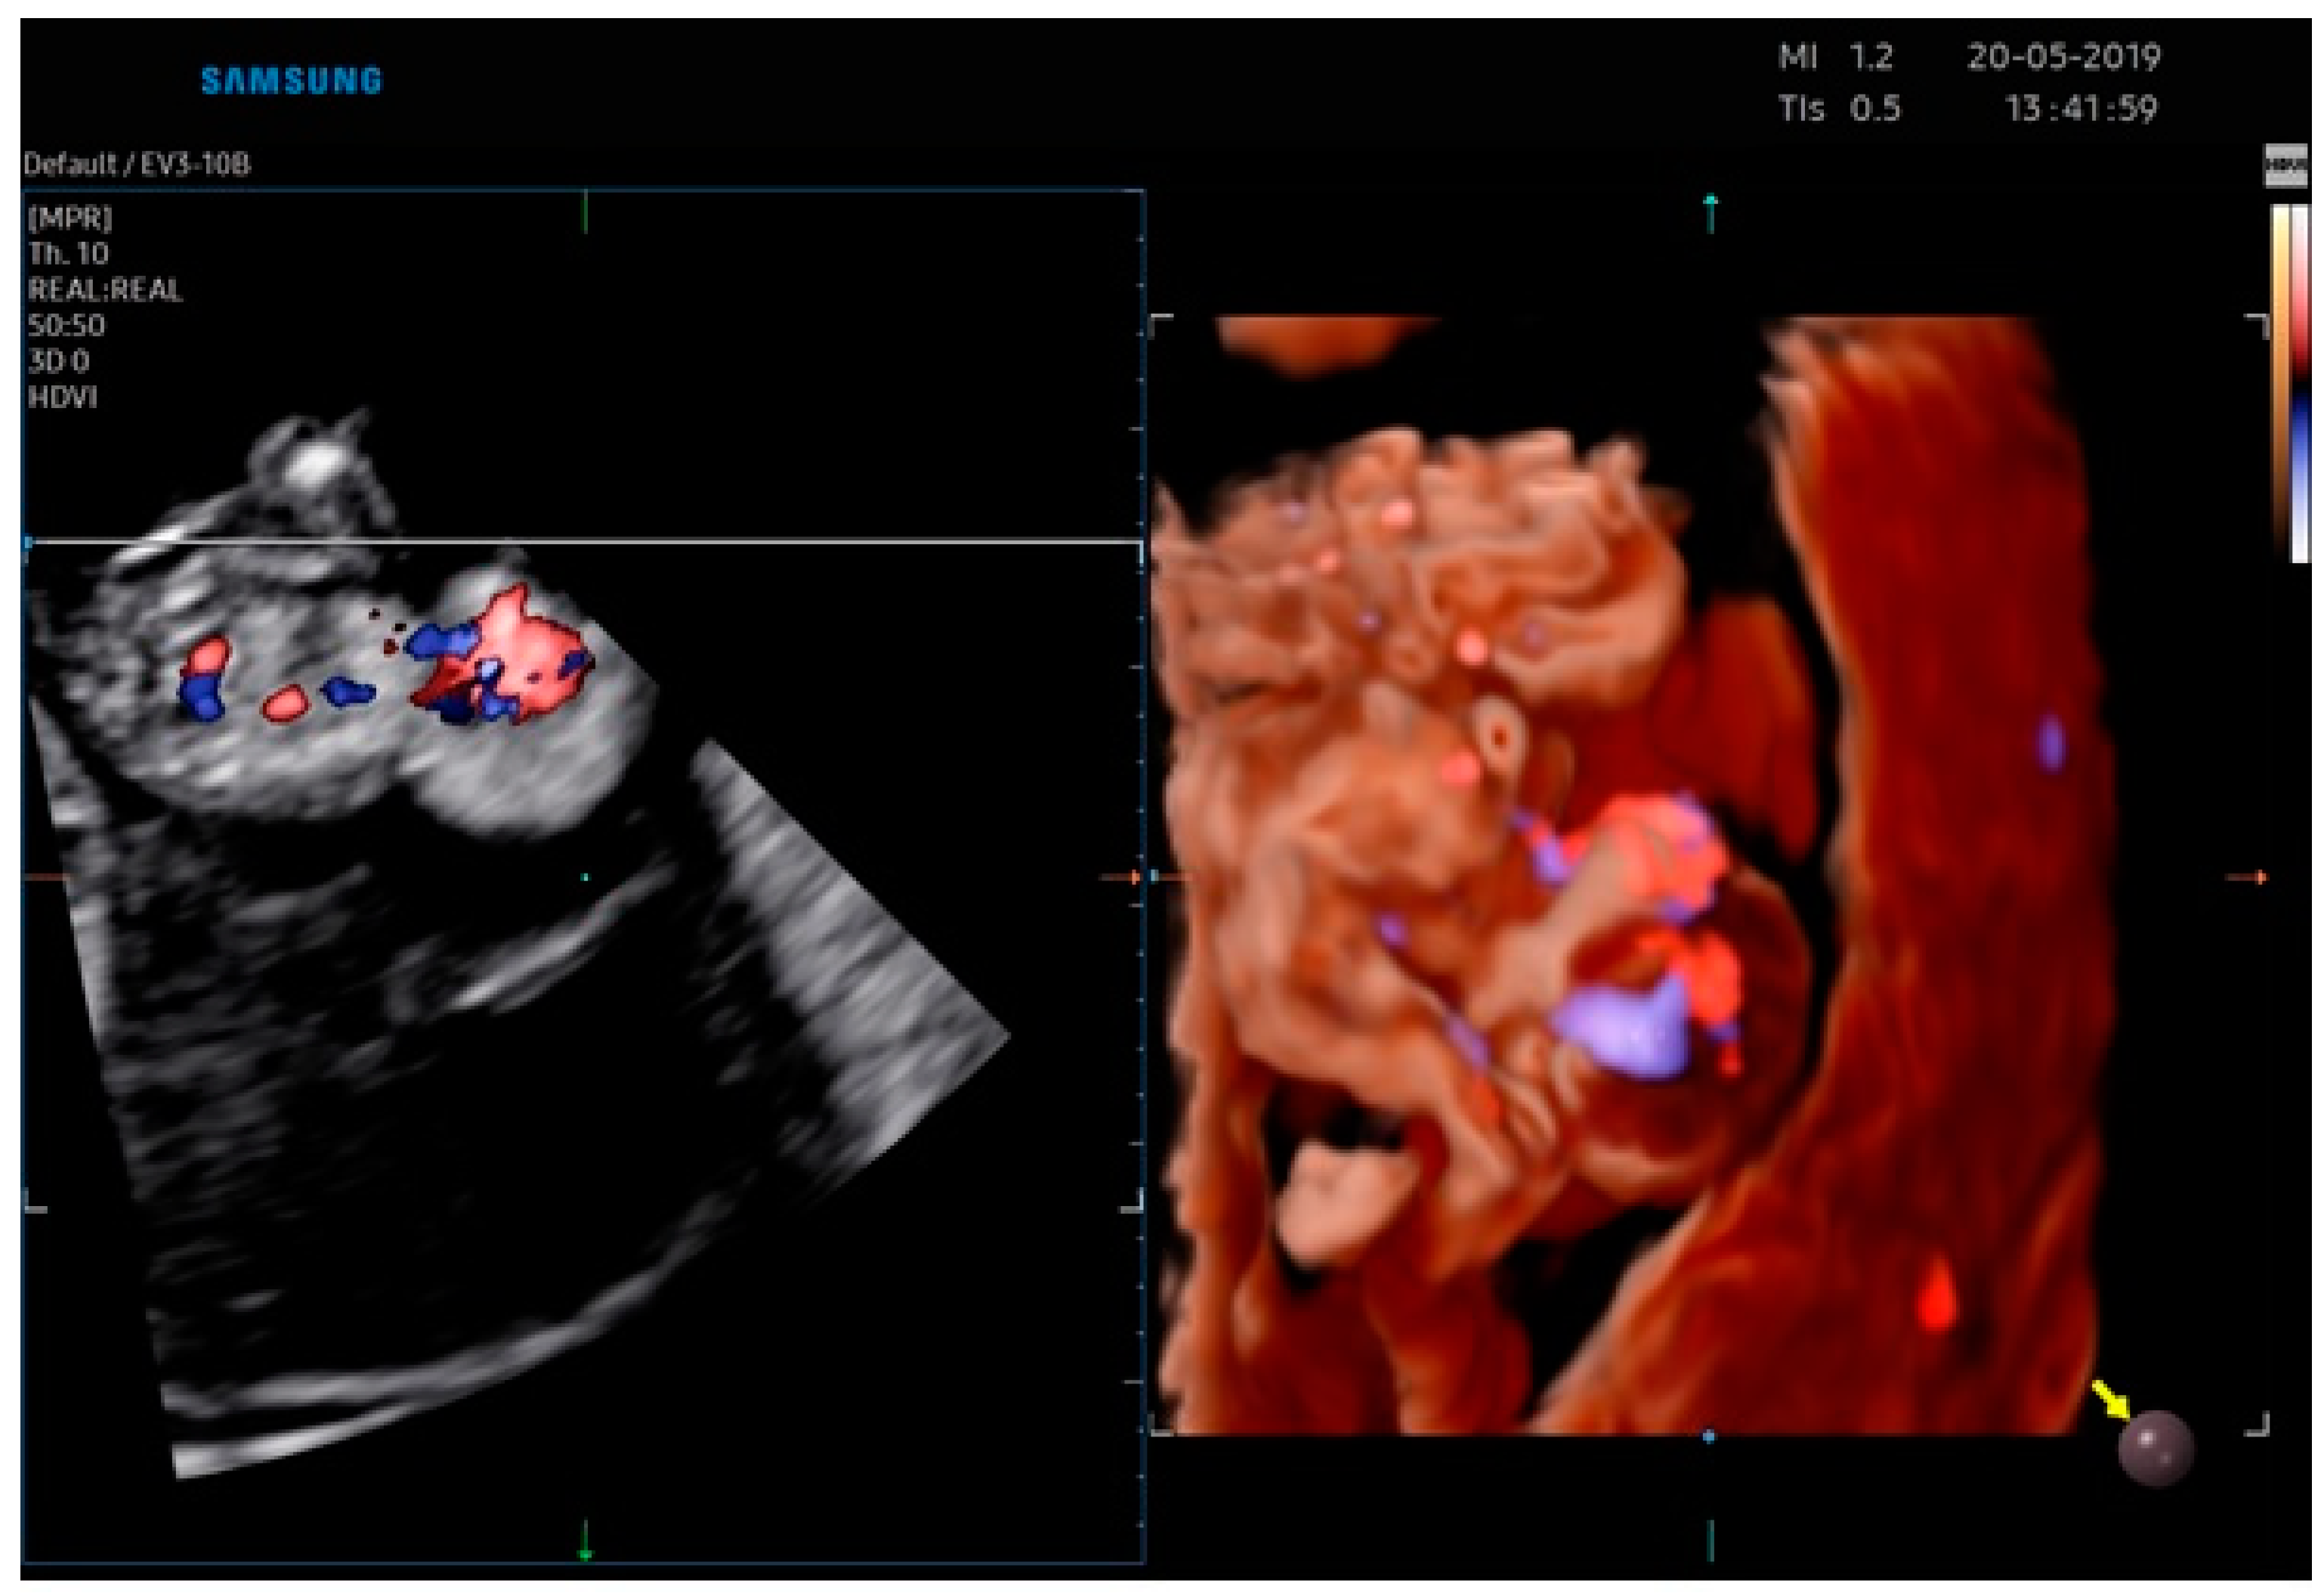

2.1. Case Report 1